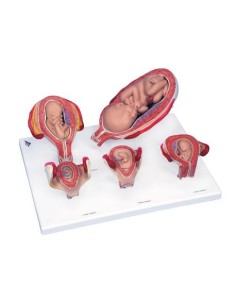

3B Modèle scientifique et gynécologique pour l'entretien avec les patientes P53

3B Scientific. Kit d'enseignement, système de reproduction femelle W40214

3B Modèle scientifique et anatomique du développement de l'embryon en 12 étapes VG391

3B Modèle anatomique scientifique du bassin gravide, décomposable en 3 parties L20

3B Bassin scientifique, anatomique Modèle pour illustrer l'accouchement L30